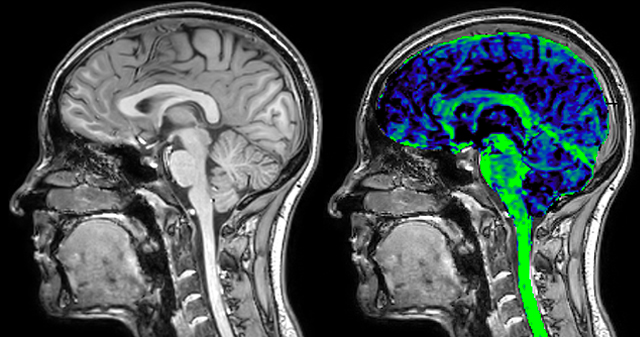

The techniques for measuring myelin have changed a lot over the years. “Since we are using the Elition, our myelin water images are much better. We're now acquiring 1 x 2 x 5 mm voxels and displaying at 1 x 1 x 2.5 mm. For a whole brain we can now measure the fraction of water in the myelin component in only about five or six minutes,” Dr. MacKay says.

of limiting MWI to the brain, even without the cerebellum, we can now spend about the same amount of time and scan the whole brain and the cervical spinal cord, which is a huge boost for us.” Dr. Rauscher says, “For MWI we perform 3D T2 with 32 or more echoes. This used to take a long time, but with Compressed SENSE we can decrease this to ten minutes for the whole head. Because of the large field of view (FOV) on the readout direction, we even get information from the brainstem, which we previously missed when we were using the GRASE approach. Having the whole head scan is nice because it has spatial resolution, orientation and FOV that are comparable to the standard 3D clinical MS scans, including the FLAIR and 3D T2, and a 3D T1 for brain volume.”

T1 - weighted

Myelin water imaging (echo 1)

With SENSE

With Compressed SENSE

Acquired resolution:

1 x 2 x 5 mm3

→

1.5 x 2 x 3 mm3

Number of echoes:

32 or 48

→

56

Echo spacing:

10 ms or 8 ms

→

7 ms

| | With SENSE | | With Compressed SENSE |

| Acquired resolution: | 1 x 2 x 5 mm3 | → | 1.5 x 2 x 3 mm3 |

| Number of echoes: | 32 or 48 | → | 56 |

| Echo spacing: | 10 ms or 8 ms | → | 7 ms |

T1 - Weighted, Myelin Water Fraction Superimposed

Spinal cord coverage

Smaller, more isotropic voxels

Excellent detail in quantitative maps

Images courtesy of Adam Dvorak, Department of Physics and Astronomy, University of British Columbia